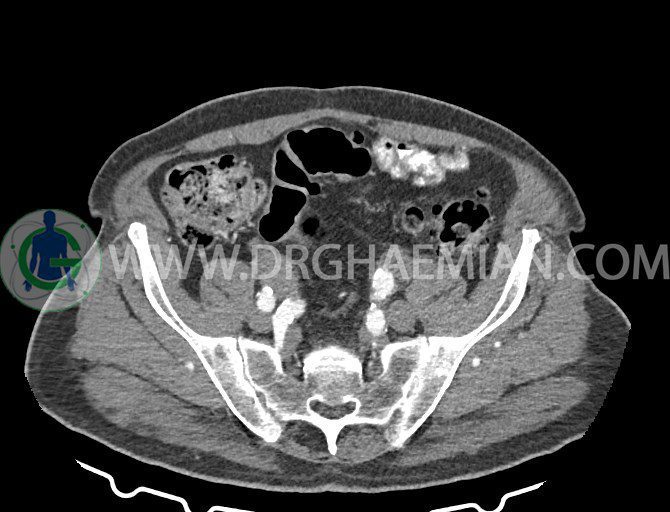

سی تی اسکن لگن یکی از روش های تصویربرداری با سی تی اسکن است. این روش با استفاده از تشعشعات تصاویر عرضی از ناحیه شکمی ایجاد میکند. در این کیس ديورتيكولوزيس، کیست های کورتیکال در هر دو کلیه، لنفادنوپاتی، کلسیفیکاسیون دیواره آئورت و شریان ایلیاک، تغییرات DJD ناحیه توراکولومبار و پروستات بزرگتر از عادی دیده می شود.

در سي تي اسکن اسپيرال شکم و لگن با و بدون کنتراست خوراکی و وريدی (مولتي ديدکتور 16 با مقاطع ظريف و بازسازي هاي ساژيتال و کرونال):

– کلسيفيکاسيون ديواره آئورت و شريان ها ايلياک همراه با نشانه هاي ترومبوز مورال در بيفورکاسيون ائورت با امتداد به پروگزيمال هاي شريان هاي ايلياک

لنفادنوپاتي به ابعاد mm 22 x 25 مجاور شريان ايلياک خارجي چپ و به ابعاد mm 17 x 28 مجاور شريان ايلياک خارجي راست

– پروستات به ابعاد mm 45 x 54، بزرگ تر از نرمال

مشهود است.

– مطابقت سونولوژيک و بررسي بافتي لنفادنوپاتي پيشنهاد مي شود . (sono guided CNB)